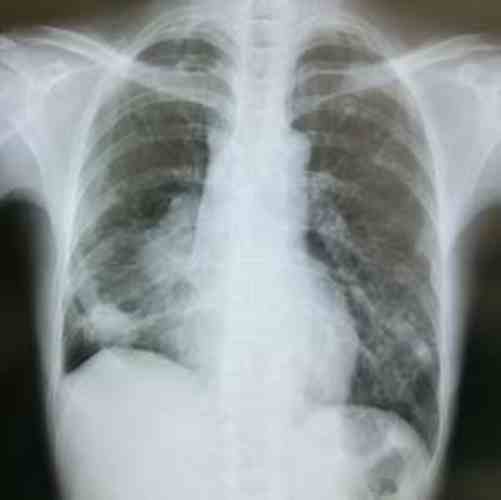

폐암 4기는 암이 이미 다른 장기로 전이된 상태를 의미하죠. 의사의 진단을 받으신 환자분들과 가족들은 가장 먼저 ‘생존율’에 대해 궁금해하시고 큰 걱정을 하시게 되는데요. 과거에는 폐암 4기의 예후가 매우 어렵다고 여겨졌지만, 근 몇 년간 폐암 4기 생존율 변화 데이터로 보는 치료의 희망적 연구가 등장하면서 생존율은 크게 향상되고, 치료의 희망도 함께 커지고 있습니다.

폐암 4기, 즉 원격 전이된 폐암의 경우, 과거에는 5년 상대 생존율이 한 자릿수에 머물렀습니다. 하지만 2010년대 이후 신약 개발의 성과가 반영되면서 생존율은 지속적으로 증가하는 추세입니다. 특히 환자 개개인의 유전자 변이에 맞춘 맞춤형 치료가 생존율 향상에 결정적인 역할을 하고 있답니다.